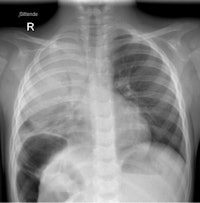

Pleural empyema is increasingly being seen, both as a result of improved diagnosis and the reduced number of patients treated with antibiotics, according to de Lange. Chest radiographs and ultrasound exams should be the first exams ordered.

A CT scan should be ordered only when ultrasound and chest x-ray exams do not distinguish a loculated empyema from an intraparenchymal abscess or a cavitary necrosis/necrotizing pneumonia. Contrast-enhanced CT exams may be required to identify the position of drains, loculations, and parenchymal complications in patients who do not respond to treatment. Exposure to the CT radiation dose may also be warranted when imaging suppurative lung parenchymal complications because of CT's sensitivity and ability to detect and establish the extent of the complication.